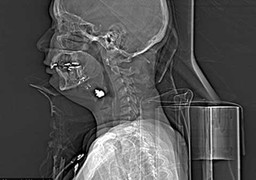

(VTC News) - Hình ảnh X-quang cho thấy viên đạn bị mắc kẹt trong cổ nạn nhân sau khi cô này bị bắn xuyên má trôi xuống cổ.

Những nạn nhân bị đâm thủng tim, máy cuốn nát chân, lòi ruột, thậm chí đạn bắn tưởng như cầm chắc cái chết nhưng vẫn thoát án tử một cách diệu kỳ.